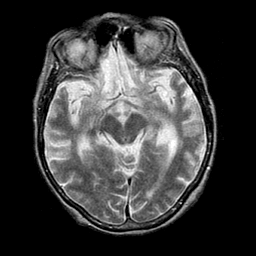

Pick's Disease, MR Study mr-t2 -- Slice #9

[Home][Help][Clinical] Slice 9